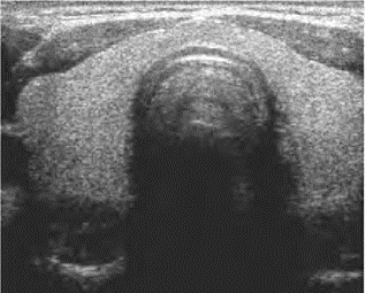

图7-9 甲状旁腺腺瘤声像图

甲状腺右叶下极后缘可见一个类圆形低回声结节,边界清楚(横切面)

超声表现:在甲状腺后缘下极,可见结节样回声,形态多样,呈圆形、椭圆形或长方形、泪珠形等。边界清晰光滑,常有包膜。内部呈均匀实性低回声,当有囊性变或出血时,可显示无回声区。CDFI:血流丰富,呈环绕或深入腺瘤内,瘤体内部可探及高速血流信号。